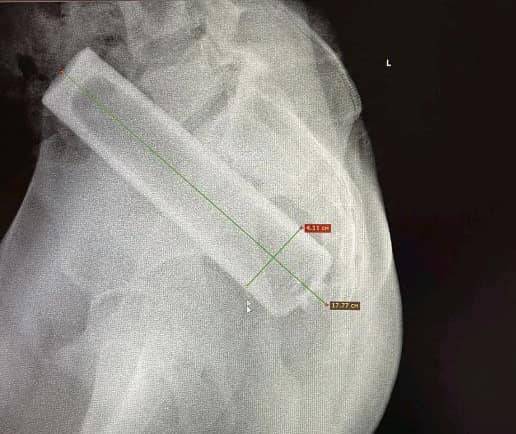

Один із останніх таких випадків стався з 16-річним хлопцем, у животі якого лікарі виявили вібратор. Три години вібратор продовжував працювати всередині пацієнта, приводячи до дискомфорту, болю в животі та кровотечі.